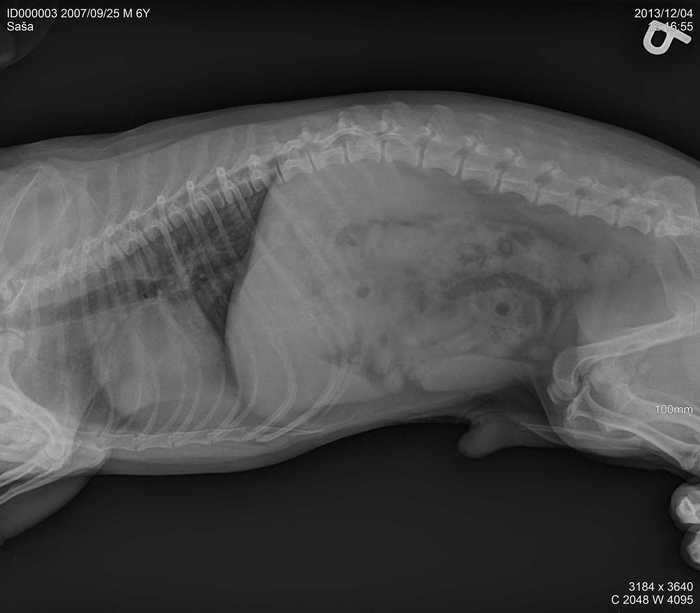

Úvod > Galerie > RTG snímky